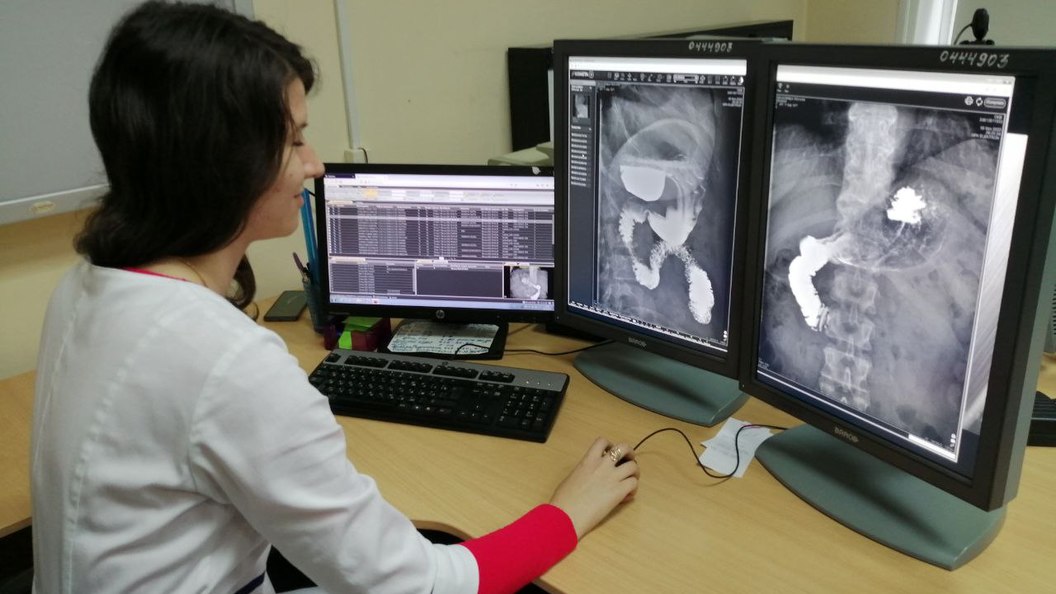

Профессиональные заболевания рентгенологов: риски и профилактика

Раздел: Путеводитель по жизни